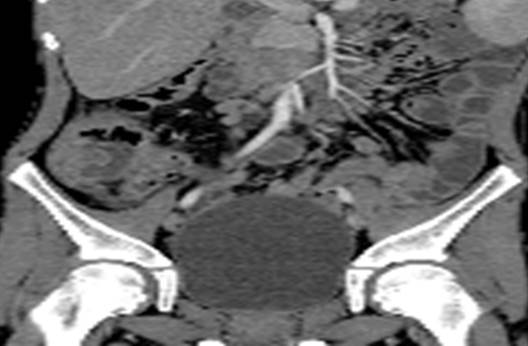

При недостаточности клинико-лабораторных и ультразвуковых данных возможно использование компьютерной рентгенографии (спиральная компьютерная томография с контрастированием и т.д.) (Рис. 4).

Рисунок 4. Аппендикулярный инфильтрат. Компьютерная томография с контрастированием[4].